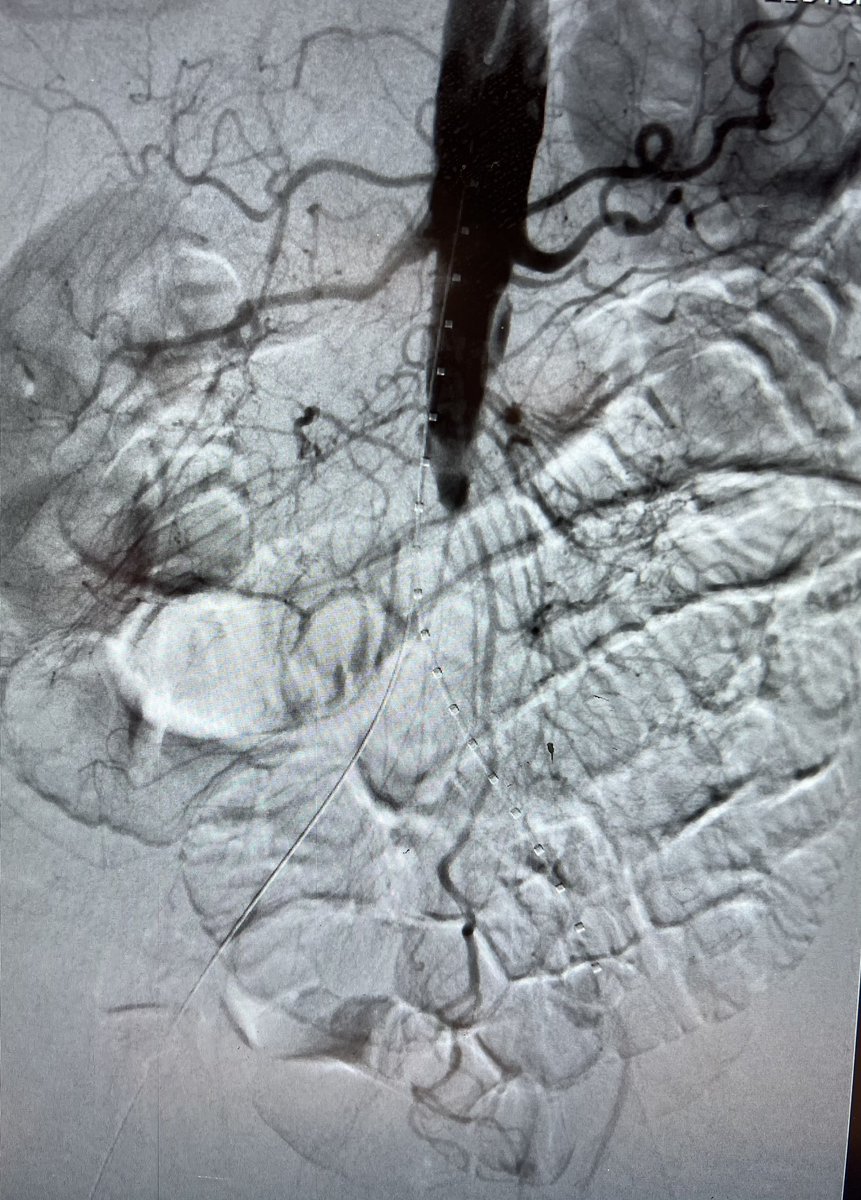

Genicular Artery Embolization for knee osteoarthritis. No skin mottling or ulcers. @IrColorado

11

19

179